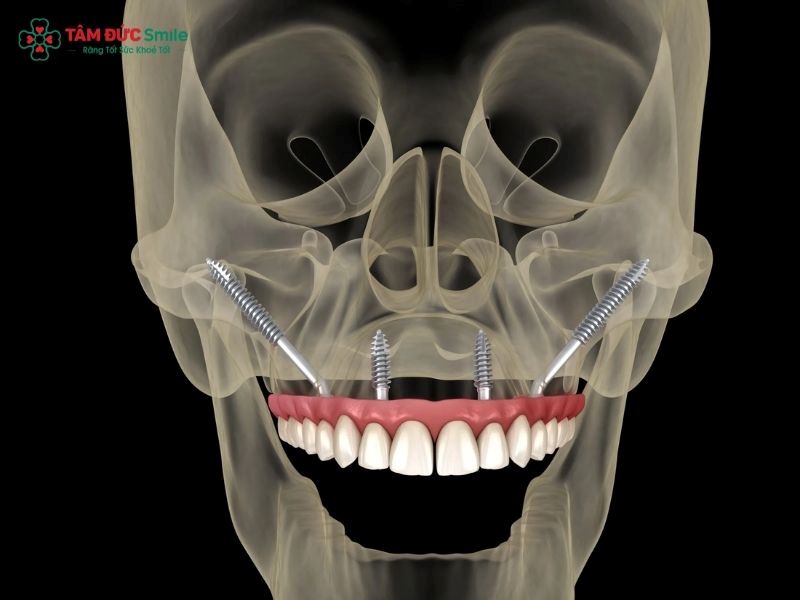

Zygomatic dental implants are a specialized form of dental implant therapy designed for patients who suffer from severe upper jaw bone loss and are not suitable candidates for traditional dental implants. Instead of being anchored into the maxillary (upper jaw) bone, these implants are placed into the cheekbone (zygomatic bone), which is significantly denser and more stable.

From a clinical perspective, the definition of zygomatic implants centers on their extra-long implant design. Unlike conventional implants that typically range from 8–15 mm in length, zygomatic dental implants can extend up to 30–55 mm. This extended length allows the implant to bypass the resorbed maxillary bone and gain firm anchorage in the zygoma, a strong facial bone that rarely undergoes resorption even in long-term edentulous patients.

3.2 Surgical Placement of Zygomatic Implants

During zygomatic implant surgery, the implants are placed through the upper jaw and anchored into the zygoma. The procedure is usually performed under general anesthesia or deep sedation and takes approximately 3 hours, depending on case complexity.

Key surgical characteristics include:

- Use of extra-long implants

- Angled insertion to maximize stability

- Avoidance of bone grafting

- Immediate or early loading possibilities

Thanks to the density of the cheekbone, primary stability is often excellent, allowing for immediate provisional restoration in many cases.

5.3 Full-Arch Rehabilitation Possibilities

Full-arch rehabilitation is one of the most common applications of zygomatic dental implants. By combining zygomatic implants with conventional implants in the anterior maxilla, clinicians can restore a full upper arch with a fixed prosthesis.

5.4 Facial Aesthetic Improvement

Beyond oral function, zygomatic dental implants contribute to facial aesthetics by supporting facial tissues and preventing further collapse of the midface.